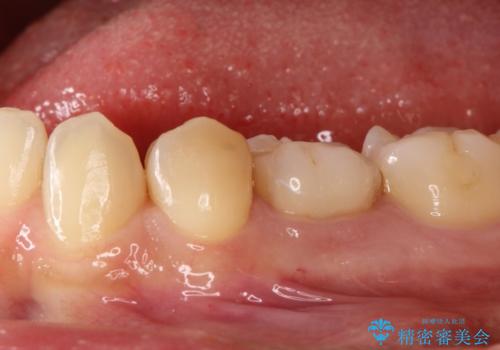

【セラミックインレー】虫歯の治療

- 定期検診にてむし歯を認めたため、セラミックインレーにて修復を行いました。

e-max プレスインレーにて修復治療を行っているため適合性及び審美性の高い治療を行うことができます